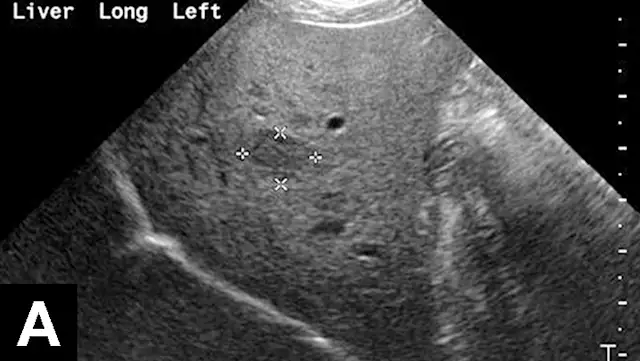

Figure 1A

In each of these cases, histologic diagnosis was made using fine-needle aspirates of the liver (vacuolar hepatopathy, hepatic lipidosis, acute severe neutrophilic hepatitis, respectively). Transverse image (A) of the left side of the liver in a normal dog showing hepatic vein (arrows) and portal vein (arrowheads). Hyperechoic liver (B) secondary to glycogen accumulation resulting from Cushing’s disease in a dog. Note the decrease in portal vascular markings. Hyperechoic and hyperattenuating liver (C) secondary to hepatic lipidosis in a cat. Note the hypoechoic falciform fat in the near field (≤1.5 cm deep) relative to liver echogenicity. In addition, there are some contact artifacts resulting in hyperechoic lines as well as the normal lines of abdominal musculature in the extreme near field (<0.5 cm). In normal cats, falciform fat and hepatic echogenicity are isoechoic to each other. In the far field, hyperattenuation of the ultrasound beam results in image dropout (starting at a depth of 3.5 cm). Hypoechoic liver (D) secondary to acute hepatitis in a dog. Note the marked decrease in echogenicity relative to the spleen.